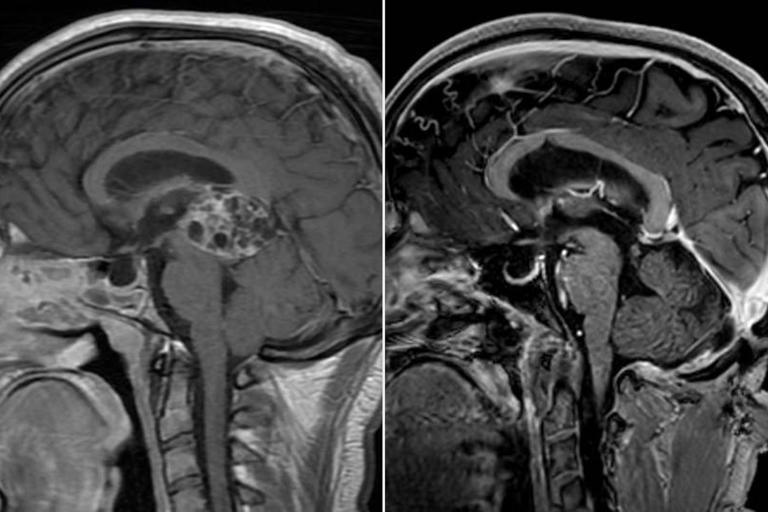

Conceptual Mri Scans Of A Brain Disorder by Simon Fraser / Science ...